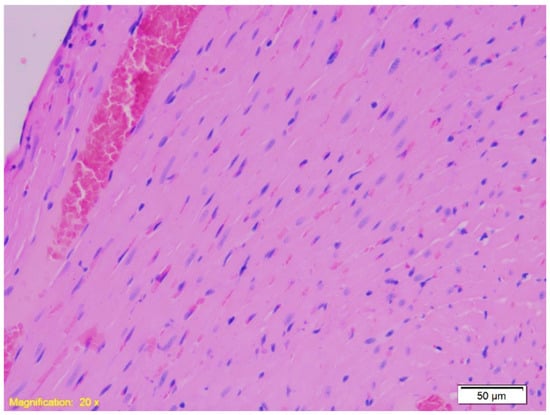

| Gastro-esophagus | Muscle layer hypertrophy, congestion, marked subepithelial eosinophilia. | Similar findings as Group K. | Similar findings as Group K. |